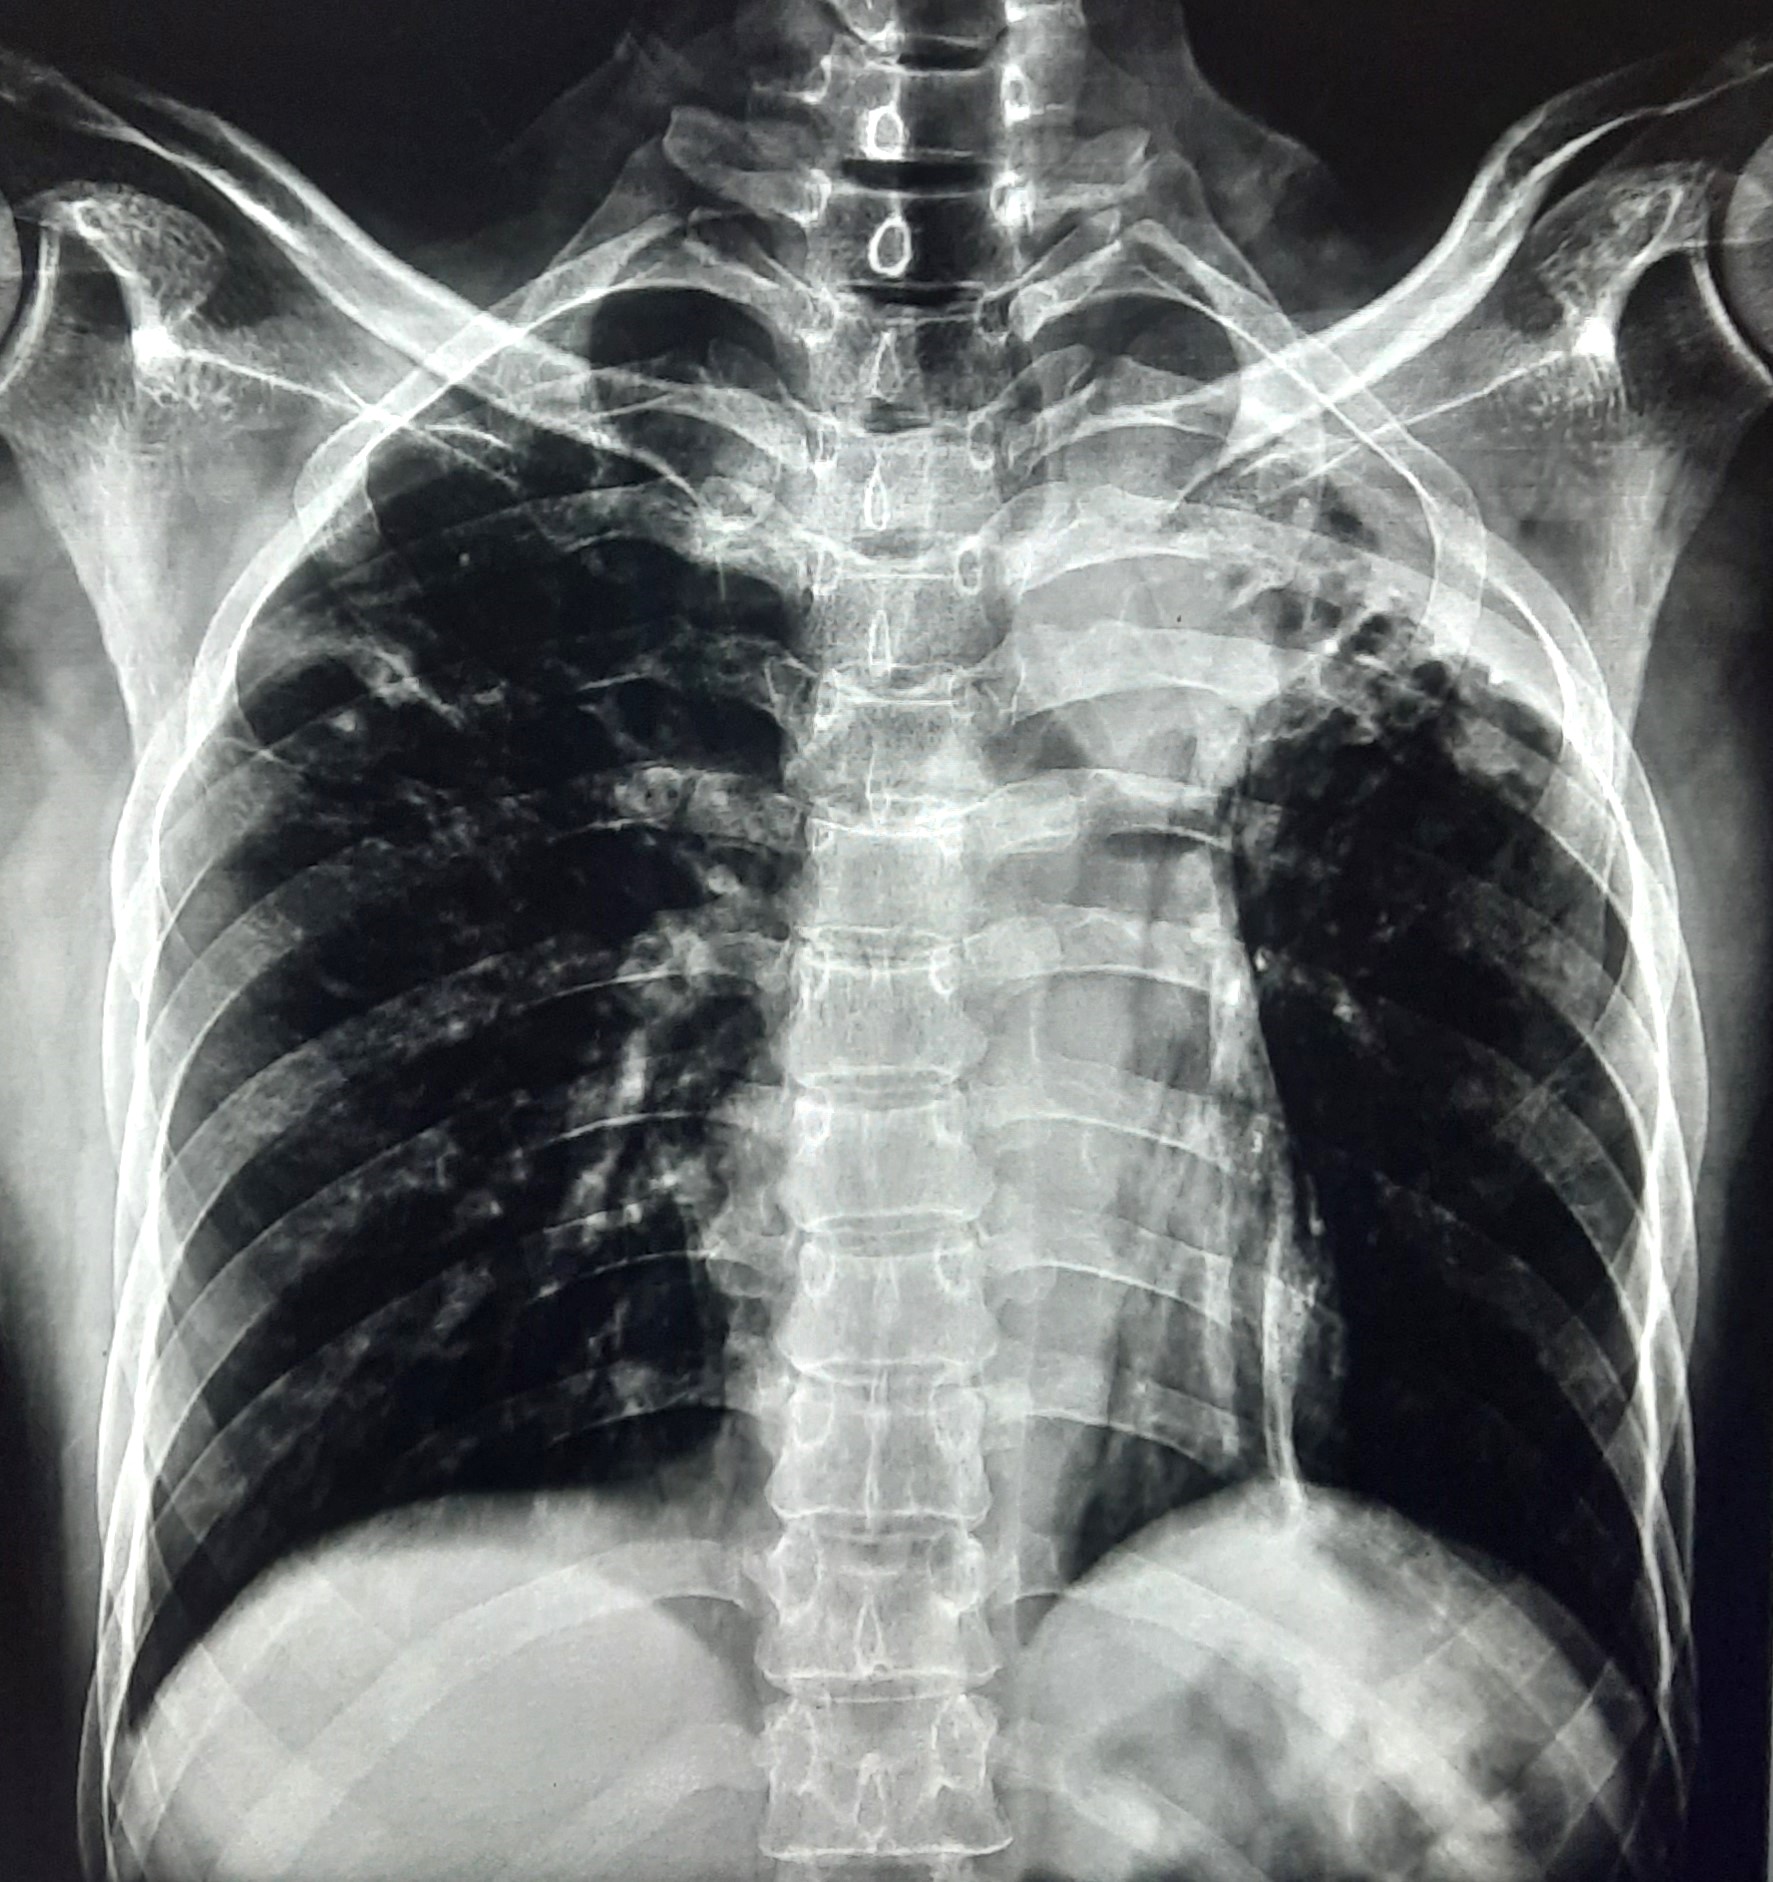

| 132 | IGGMC, Nagpur, Nagpur | P2 | 29-4340 | Ritesh Chaudhary | Consent taken on Paper | 30 Yrs. |

Provisional Diag : Post TB Sequelae

Final Diag : Post TB sequalae With Fibro Cavitary Changes |

Post TB Sequelae | Bilateral Upper Zone Fibro Cavitary Changes With Right Upper Zone Fungal Ball With Bilateral Haziness With Tenting Of Diaphragm | Abnormality visible on x-ray |